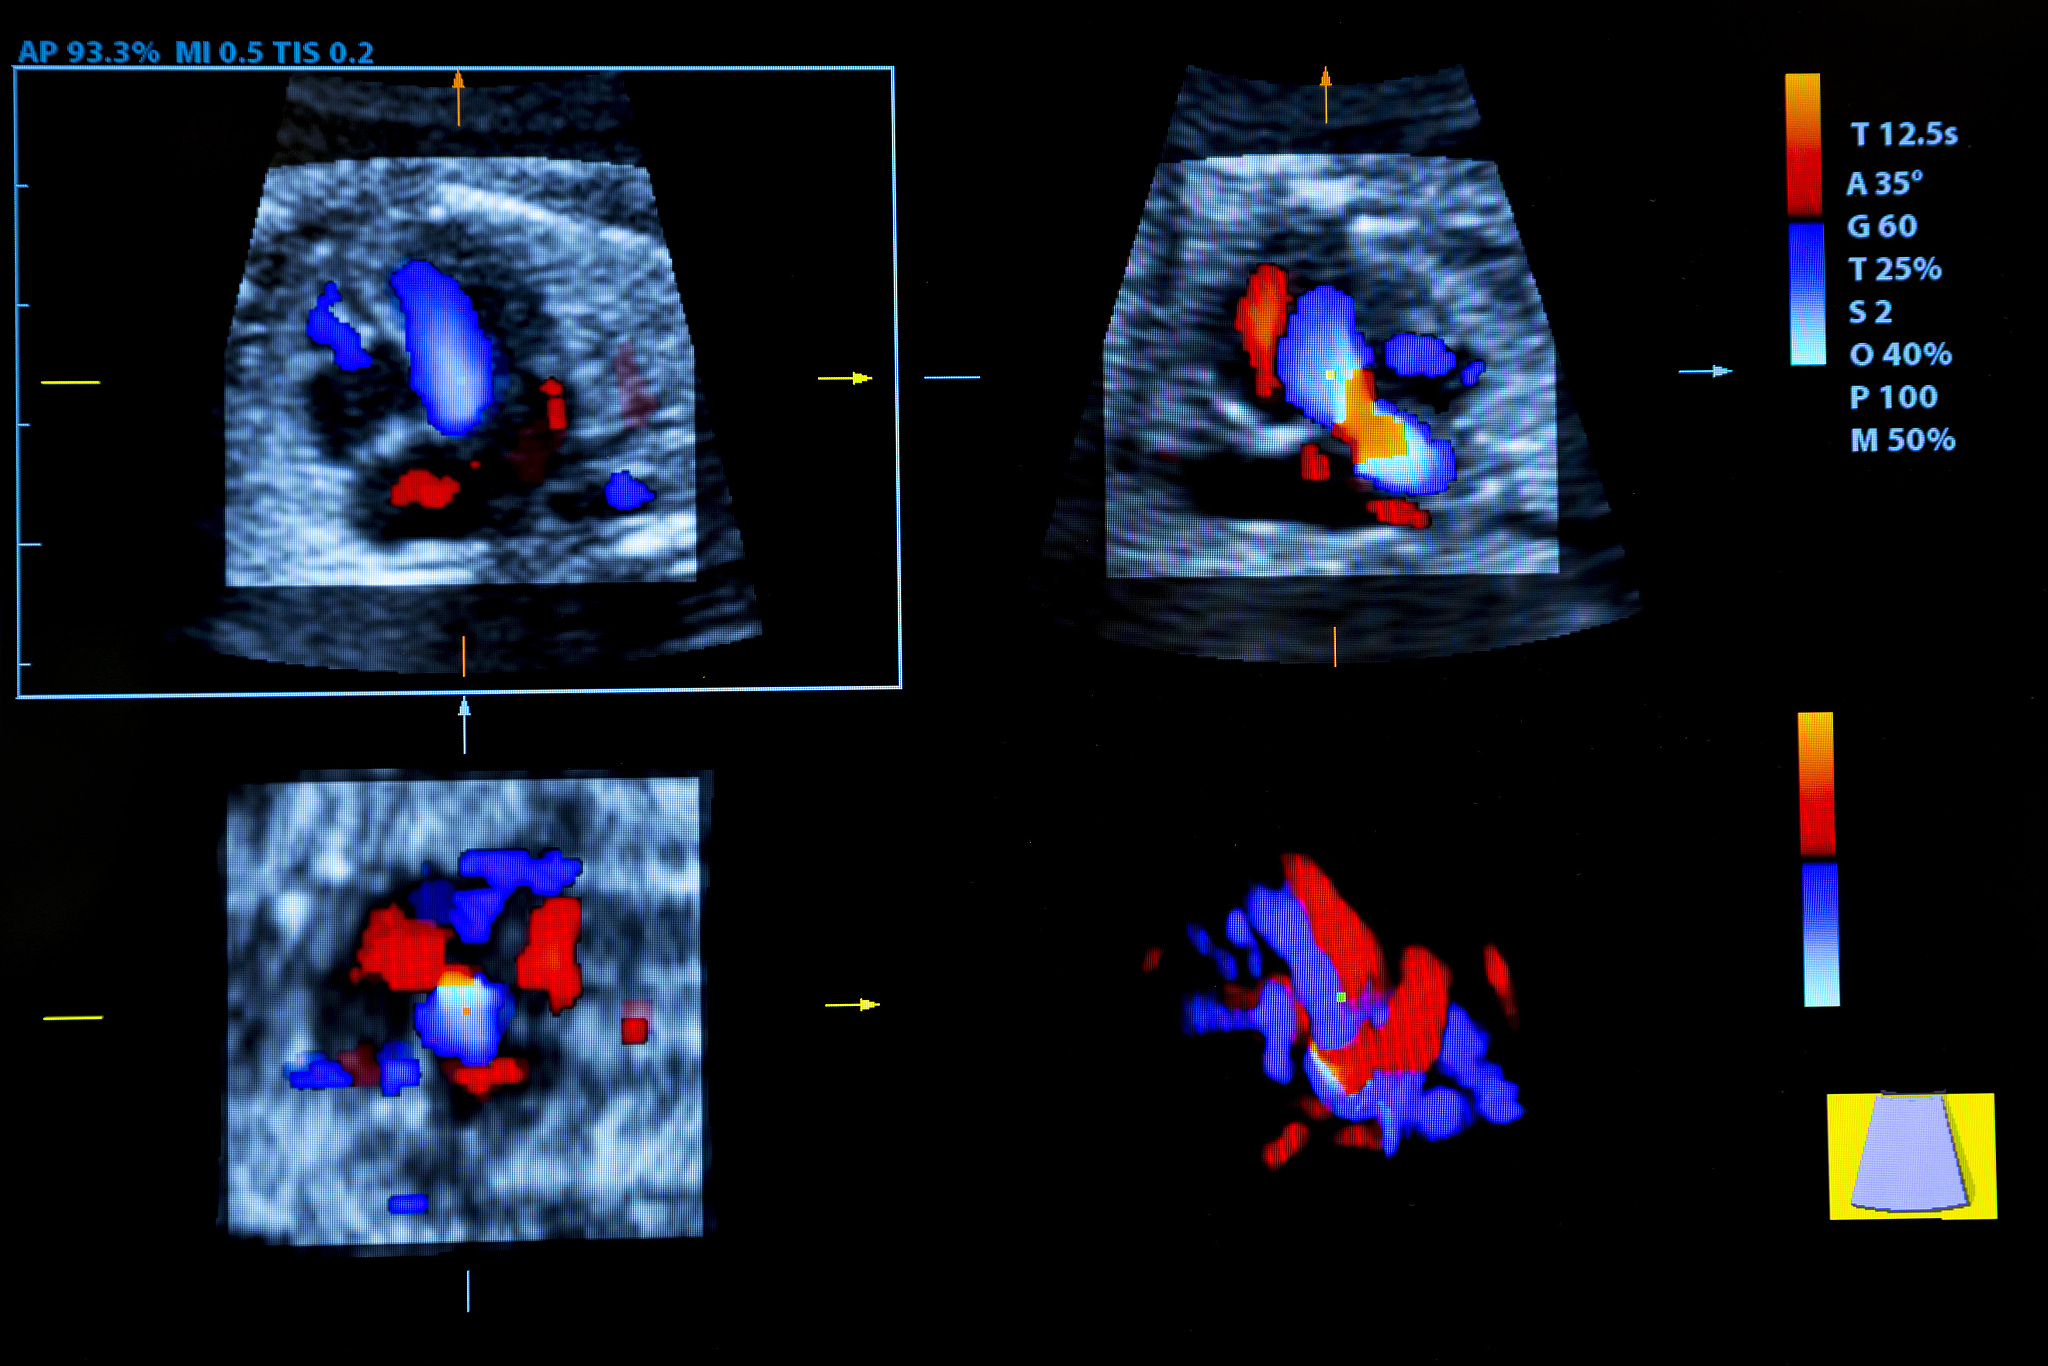

因此,考虑到急性中风患者易受损颈动脉斑块破裂的潜在风险,对其进行评估至关重要,而增强超声成像作为一种有价值的诊断工具。

翻译:Consequently it is crucial to consider the potential of vulnerable carotid artery plaque rupture in acute stroke patients with contrast-enhanced ultrasound serving as a valuable diagnostic tool